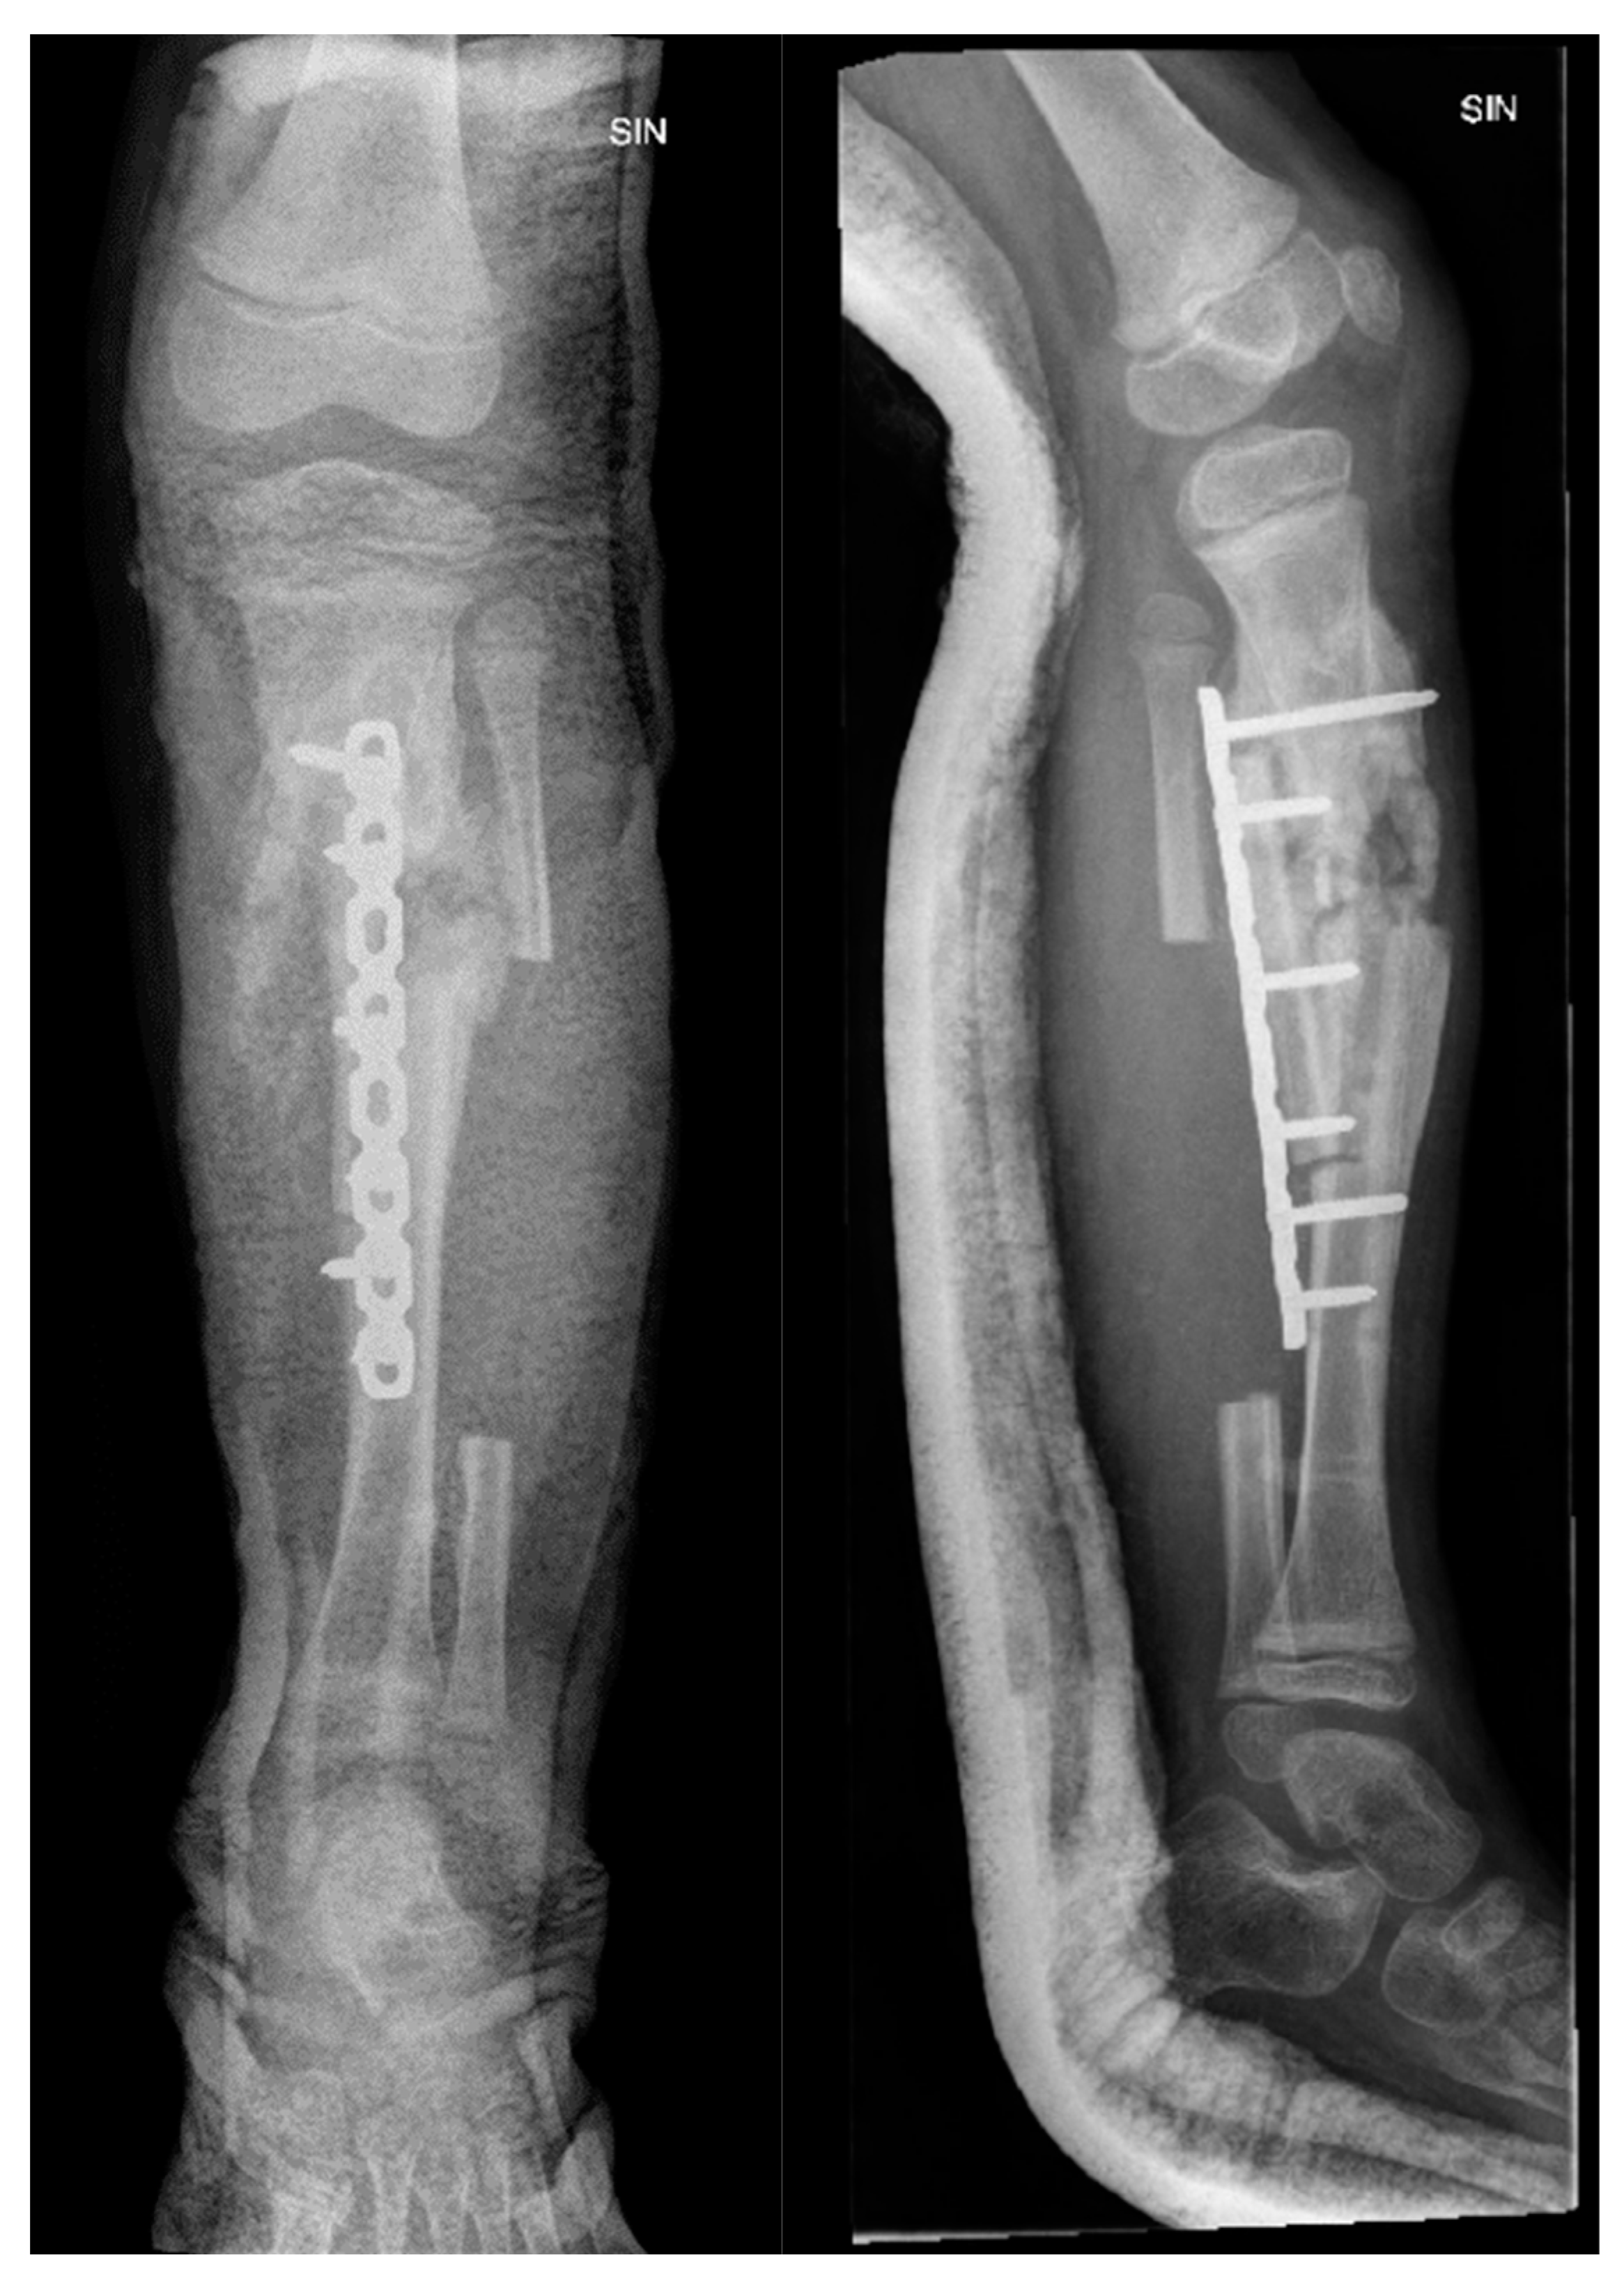

A month later, the patient was admitted for planned surgery - lower leg reconstruction. The patient underwent resection of the tibial pseudarthrosis, plasty with a vascularized fibular graft, and osteosynthesis with a locking plate (Figure 6).

Figure 6. X-ray examination of left lower leg in AP and lateral projections shows posttraumatic chronic osteomyelitis of left tibial diaphysis. After fixation with a locking plate and implantation of resected fibula diaphysis fragment, consolidation forms near implanted bone, with slightly increased soft tissue calcifications and sclerosis.